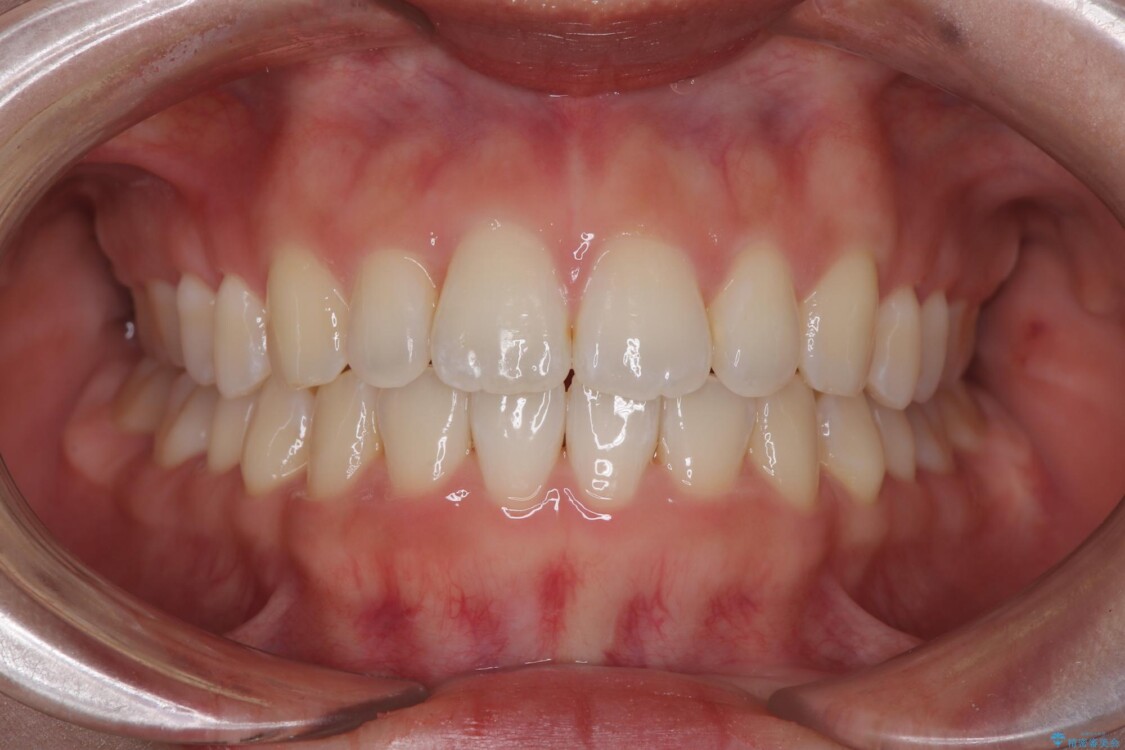

治療終了時

前歯が自然なアーチにきれいに並び、正中(上下の中心線)も整い、咬み合わせも良好です。

側方拡大することで、非抜歯であるにも関わらず前歯が前方に出ることなく、バランスの良い仕上がりとなりました。

「矯正装置が目立たず、思ったより短期間で仕上がりに満足しています。鏡を見るのが毎日楽しみになりました!」とうれしいお言葉をいただきました。

治療後

• 目立ちにくい表側装置で1年完了!狭いアーチを側方拡大し前歯のデコボコを整えた症例 治療後画像